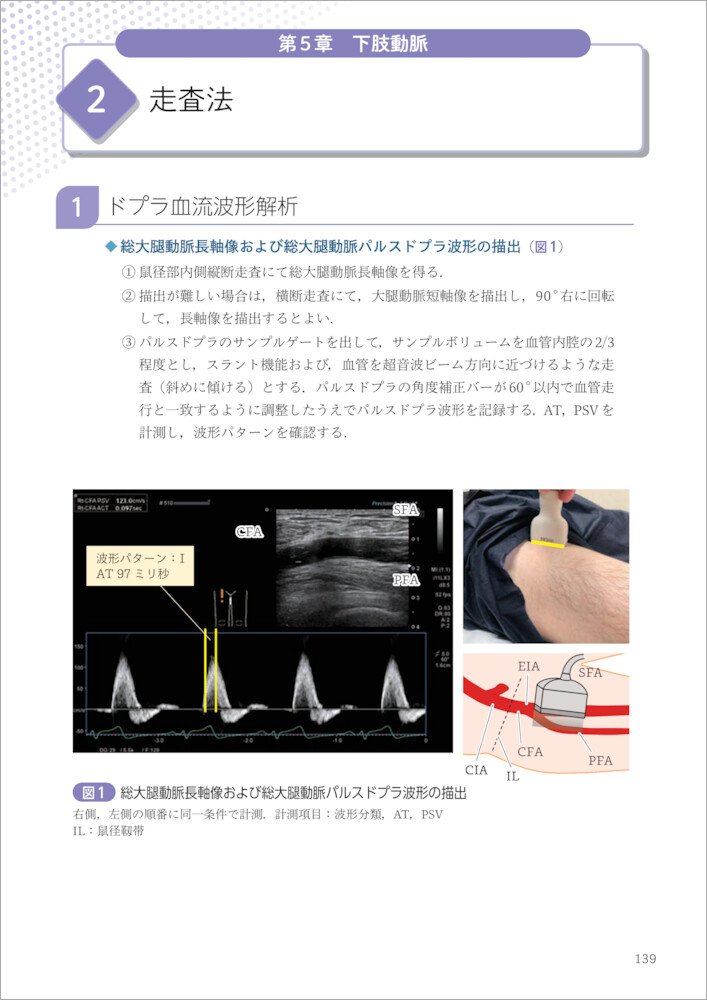

血管エコーパーフェクトガイド―動脈硬化の早期発見 (循環器臨床

血管エコーパーフェクトガイド―動脈硬化の早期発見 (循環器臨床,

血管エコーパーフェクトガイド―動脈硬化の早期発見 (循環器臨床, 血管年齢・頸部エコー・動脈硬化について | 名古屋市昭和区 横山,

血管年齢・頸部エコー・動脈硬化について | 名古屋市昭和区 横山, ストップ!動脈硬化「危険を予測 最新検査」 - きょうの健康 - NHK,

ストップ!動脈硬化「危険を予測 最新検査」 - きょうの健康 - NHK, 循環器検査 | 名古屋循環器科・内科 | 中村区名駅,

循環器検査 | 名古屋循環器科・内科 | 中村区名駅, 頸動脈エコーと動脈硬化検査 | 川崎市幸区の川崎中央クリニック,

頸動脈エコーと動脈硬化検査 | 川崎市幸区の川崎中央クリニック, 血管年齢 - 高津駅前はら内科ハートクリニック,

血管年齢 - 高津駅前はら内科ハートクリニック, 動脈硬化③ - 頚動脈超音波(頚部US)検査 - | 2020年 | コラム,

動脈硬化③ - 頚動脈超音波(頚部US)検査 - | 2020年 | コラム, 四谷三丁目・四谷・四ツ谷の内科・循環器内科・外科 | まがり,

四谷三丁目・四谷・四ツ谷の内科・循環器内科・外科 | まがり, 超音波検査(エコー検査) | あさひまちクリニック|旭川市旭町,

超音波検査(エコー検査) | あさひまちクリニック|旭川市旭町, エキスパートの手元がみえる!血管エコー〜解剖・正常像で身に,

エキスパートの手元がみえる!血管エコー〜解剖・正常像で身に, 下肢血管病の診断・治療 | 青山クリニック,

下肢血管病の診断・治療 | 青山クリニック, 四谷三丁目・四谷・四ツ谷の内科・循環器内科・外科 | まがり,

四谷三丁目・四谷・四ツ谷の内科・循環器内科・外科 | まがり, 心臓・血管の専門検査 - 名古屋市名東区 内科 循環器内科 皮膚科,